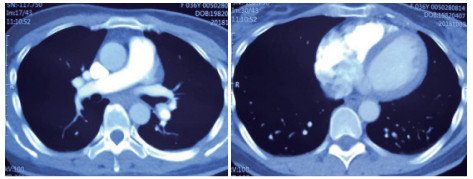

例4 62岁,女性,主诉“活动后气短20 d,加重1 d伴晕厥1次”。患者入院20 d前上近20级台阶后感气促,休息后缓解,未重视。入院前1 d,突发晕厥伴有轻微活动后明显的呼吸困难。既往:左下肢静脉曲张病史3~4年;入院40 d前患者左足跖骨骨折,接受外固定,尚未影响日常活动,未接受抗凝治疗;发现血小板减少数年(血小板维持5.5~8.6 g/L,末次于一年前血小板85 G/L),未明确原因及治疗;血气分析提示pH 7.447,PaCO2 32.2 mmHg,PaO2 85.3 mmHg,SaO2 96.8%;D-Dimer 1 947 ng/mL;FDP 22.84 μg/mL,FBG 2.05 g/L;PLT 51G/L;cTnI 0.52 ng/mL,BNP 299 pg/mL;ALT 318 U/L,AST 300 U/L,CREA 74.8 μmol/L,血Na+、K+、Cl-:正常范围;UCG提示:右心大,肺动脉主干轻度增宽(28 mm),三尖瓣反流(重度),反流面积13.7 cm2,TI法估计SPAP为30 mmHg、左室舒末内径35 mm、左室舒张功能受限(E/A 1:1.5)、未见节段性室壁运动障碍;双下肢静脉超声提示左侧腘静脉不完全血栓。心电图(图 12所示)提示窦性心动过速、SⅠQⅢTⅢ;CTPA显示肺动脉分叉处及双肺亚段充盈缺损(图 13所示)。

| 图 13 入院时CTPA结果显示肺动脉分叉处及双肺亚段充盈缺损 |

入院查体:神志清楚,体温36.5℃,血压120/70 mmHg,脉率110次/min,呼吸22~26次/min,指氧饱和度93%(安静,空气氧),未见乏氧征。双肺呼吸音清,未闻及干湿性啰音,心率110次/min,律齐,P2 > A2,心界无扩大,无杂音,腹软,无压痛,肠鸣音正常。神经系统未见异常。左下肢膝关节以下可见静脉曲张,双下肢无浮肿。入院诊断:急性肺血栓栓塞症(中高危);左下肢静脉曲张并血栓形成;血小板减少症;肝功能不全。处理方法及原因:患者中年,日常生活质量高;入院20 d前虽有症状,但入院1 d前明显加重并出现晕厥发作;两次D-Dimer检查均<2 000 ng/mL,与CTPA显示的血栓负荷不匹配。入院后连续两次检测血小板均低于正常(51~77 g/L)。因考虑病史较长但近期有加重、血小板低等原因系统溶栓治疗出血风险较大,所以给予导管介入碎栓并行肺动脉内溶栓治疗(r-tPA 20 mg)。溶栓2 h后患者症状明显缓解,复查D-Dimer 12 560 ng/mL,序贯肝素抗凝并复查CTPA提示原有血栓明显消失(图 14所示)。

| 图 14 介入溶栓后患者CTPA结果提示明显改善 |